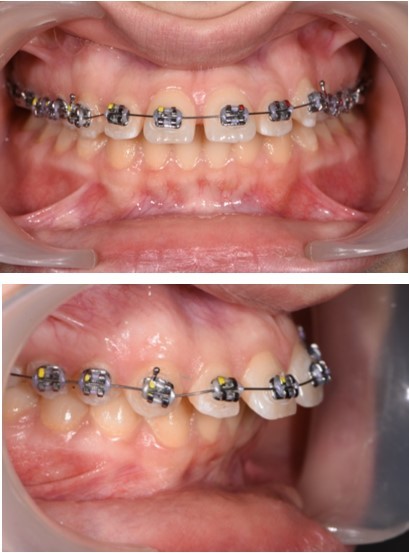

The working stage of the treatment was done with the use of a rectangular stainless steel archwire 0.019”x0.025” (Figure 5, Figure 6). Bodily movement was obtained and a minor intrusion. The incisal edges were displaced backward in order to provide a better incisal display at rest and during the smile. Unlike palatal arches, where the retraction is done by tipping the incisors, the mini implants in our case were able to provide a bodily retraction of the upper anterior teeth. Therefore, retraction was obtained with no anchorage loss. The improvement in the overjet and overbite was good.

Figure 5.Retraction of the upper incisors with elastics chains placed from crimpable hooks to orthodontic implants.

Figure 6.Significant overjet and overbite improvement after implant based orthodontic retraction.

The labial inclination of the incisors was corrected and better torque values were obtained. With the use of the temporary anchorage devices, a total of 7 mm of retraction was done in this case.

By moving the incisal edges backward, the upper lip position in regard to the upper frontal teeth was modified. The new position of upper teeth will play a major role in maintaining stability and preventing relapse. A more stable contact was obtained between the incisal edges of the lower anterior teeth and the palatal surface of the upper frontal teeth.